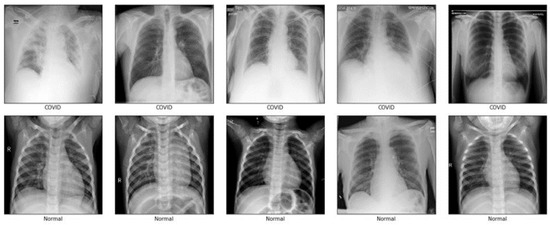

3.1. Dataset

- COVID-19 Radiography Database. Available online: https://www.kaggle.com/datasets/tawsifurrahman/covid19-radiography-database (accessed on 24 October 2022).

- Chowdhury, M.E.; Rahman, T.; Khandakar, A.; Mazhar, R.; Kadir, M.A.; Mahbub, Z.B.; Islam, K.R.; Khan, M.S.; Iqbal, A.; Al Emadi, N.; et al. Can A.I. help in screening viral and COVID-19 pneumonia? IEEE Access 2020, 8, 132665–132676. [Google Scholar] [CrossRef]

- Rahman, T.; Khandakar, A.; Qiblawey, Y.; Tahir, A.; Kiranyaz, S.; Kashem, S.B.; Islam, M.T.; Al Maadeed, S.; Zughaier, S.M.; Khan, M.S.; et al. Exploring the effect of image enhancement techniques on COVID-19 detection using chest X-ray images. Comput. Biol. Med. 2021, 132, 104319. [Google Scholar] [CrossRef]